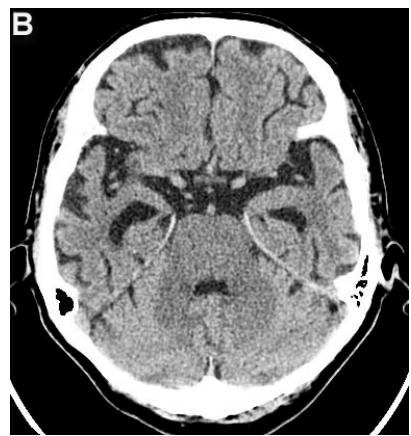

Figure 4: Same patient P., 75 years old, female TDR-3.

A. Cerebral CT before transcatheter intracerebral laser PBMT: Total atrophy of the temporal lobes is $40\%$ of the total tissue volume (TDR-3). B. Cerebral CT 12 months after transcatheter intracerebral laser PBMT: Reduction of the total atrophy of the temporal lobes by $12\%$. The patient is transferred to AD group in TDR-2 stage.